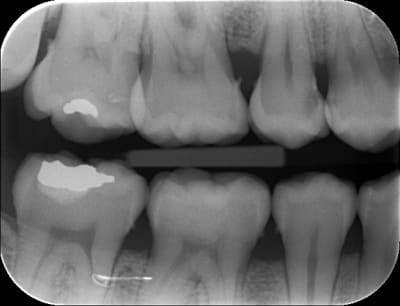

Bonjr! récente recrue sur le forum,jsuis ortho exclu et mon chir dent a proposé à mon homme un IC et une ccm pour sa 45... ça me semble un peu invasif...

-endo RAS bien que vieille

-pan lingual intact et le vestib. quasi

Il aurait fallu une photo en vue occlusale. D'après ce que je vois, un joli composite direct doit être largement suffisant. Les prémolaires du bas sont des dents qui se cassent rarement, surtout s'il n'y a qu'une cavité proximale et non MOD (en plus, largement supragingivale)

Il n'y a pas qq chose de louche au mésial de la 47 ?

et comme ceramik, il y a un truc louche sur 47

Refaire aussi la 47 (reprise de carie) et la 46 qui sont dégueulasses.

Pour la 45, un truc sans tenon (soir un compo direct avant de prendre l'empreinte pour 46, soit un inlay).